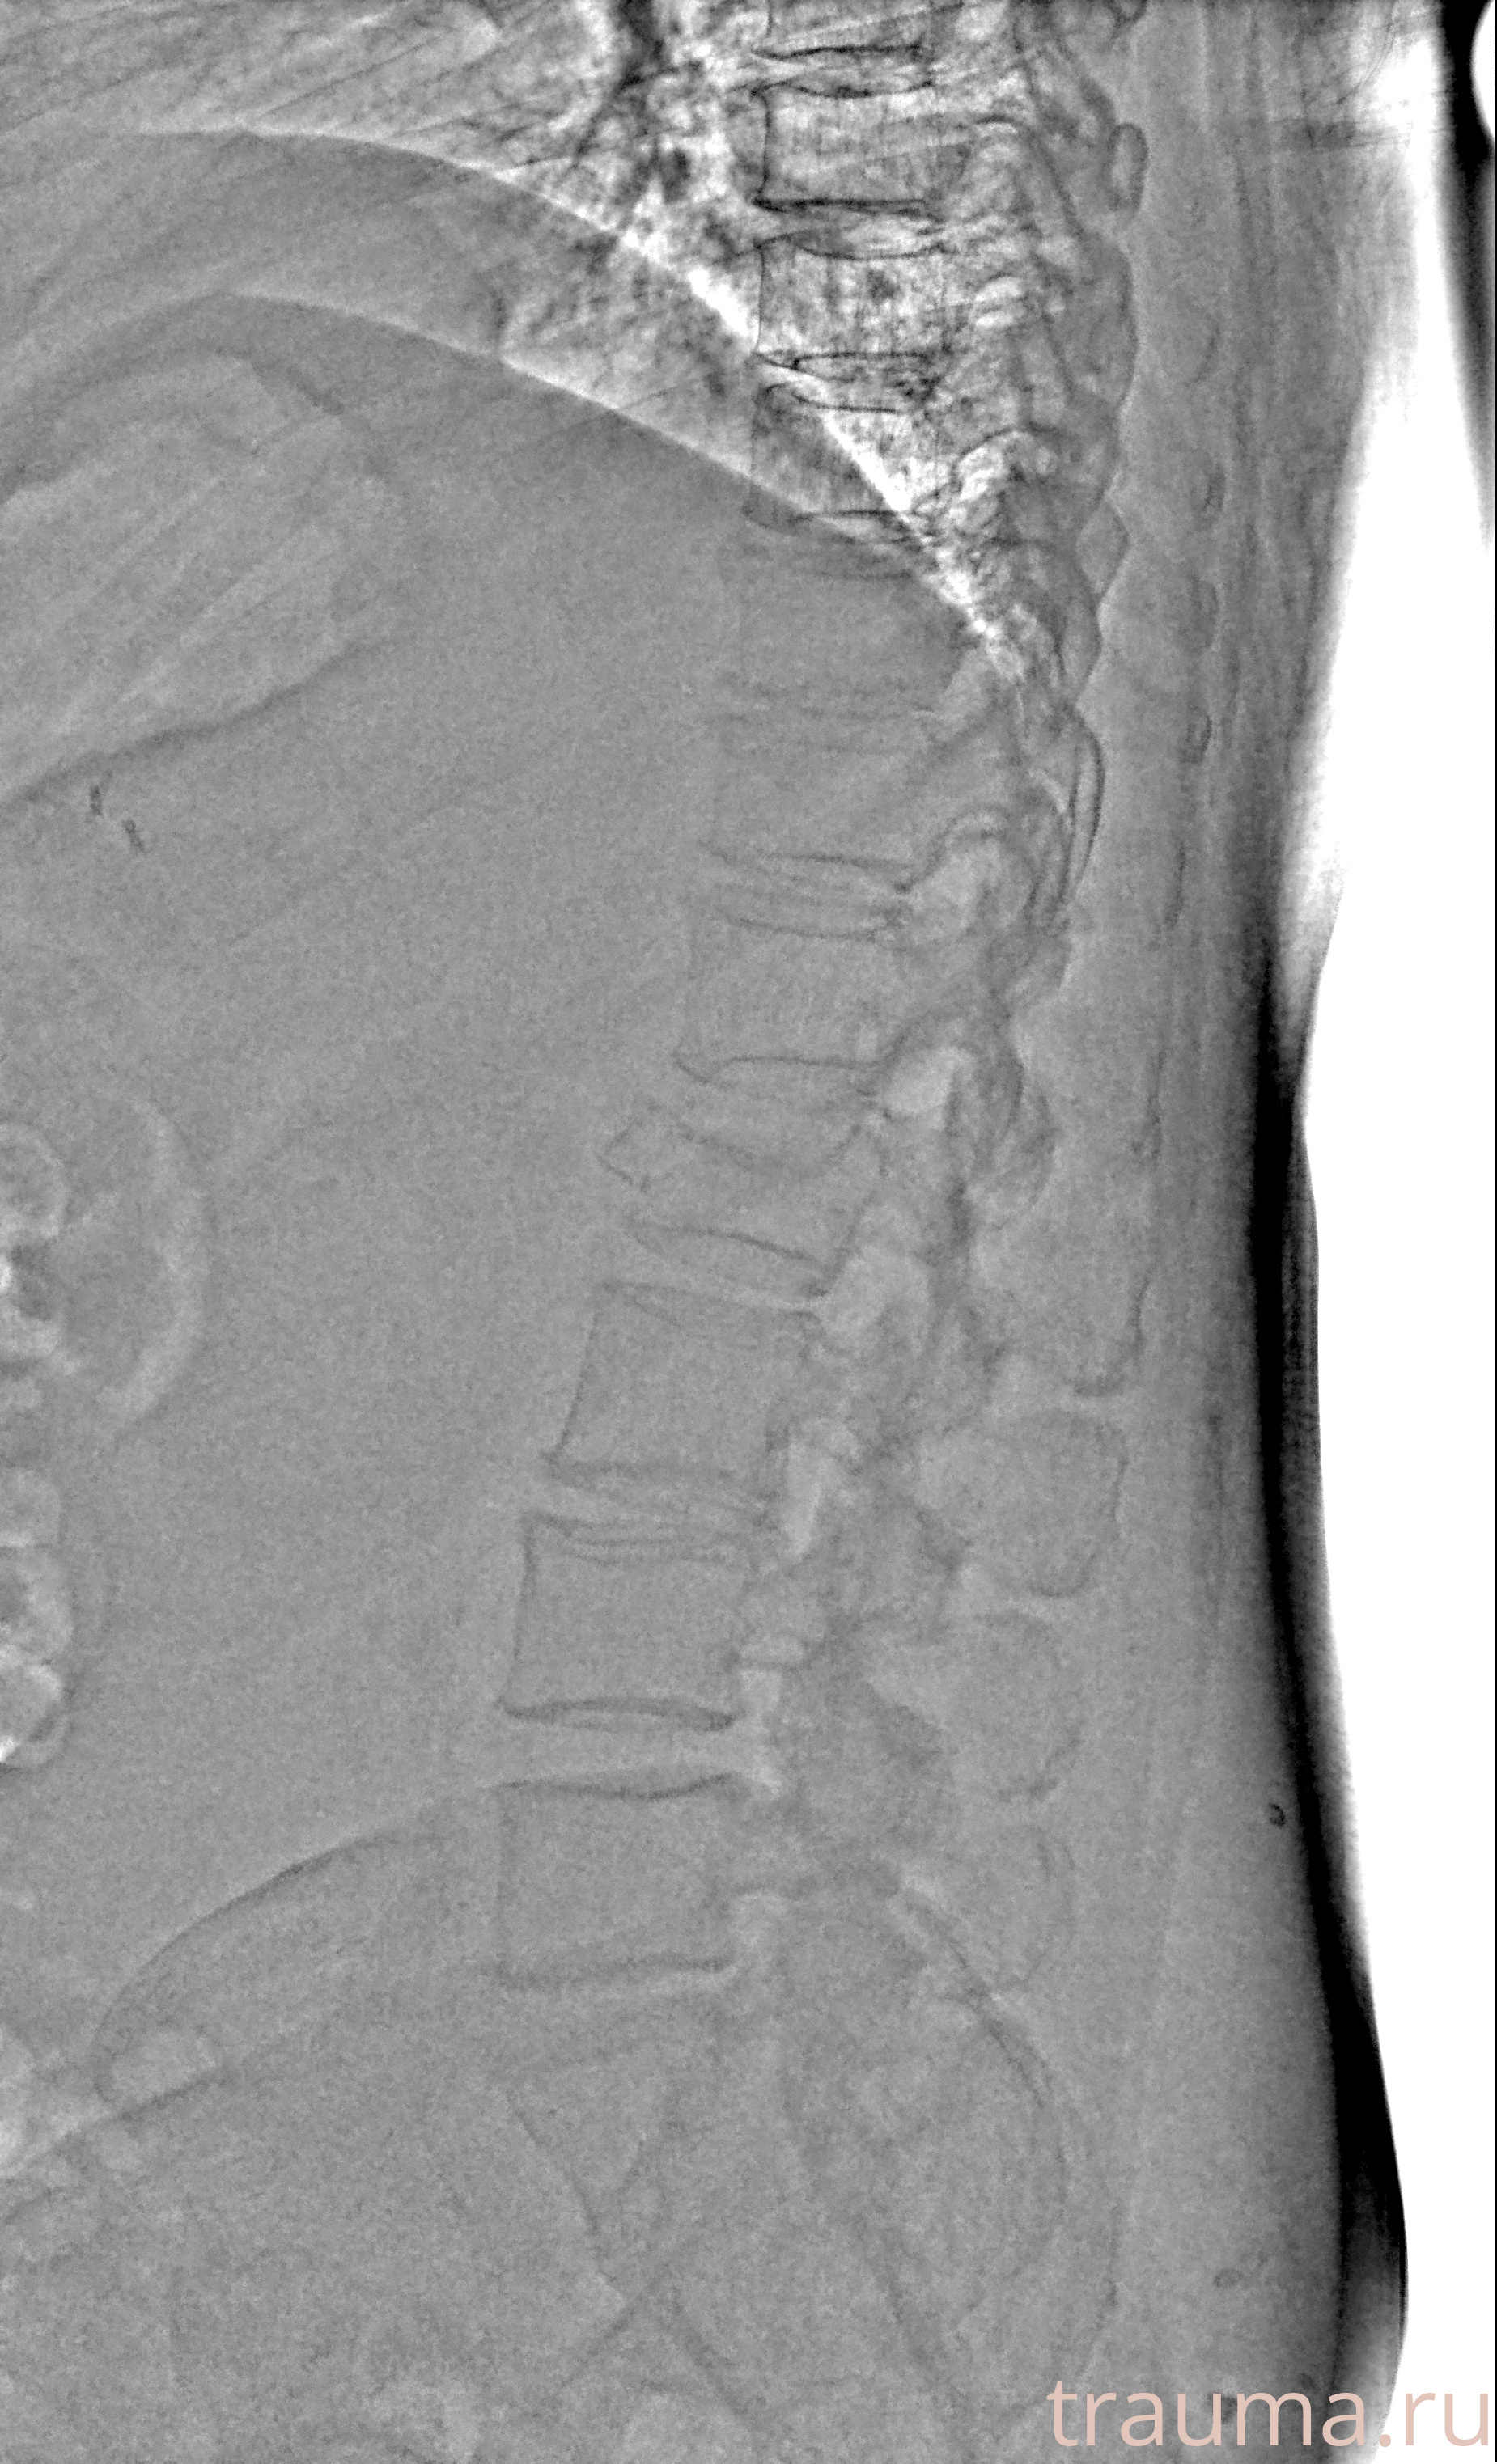

Рентгенограммы

Рентген на дому: по вашему адресу приезжает врач-рентгенолог, травматолог-ортопед с мобильным рентгеновским аппаратом, проводит диагностику травмы или заболевания, делает необходимые рентгенограммы, дает рекомендации по дальнейшему лечению. Получить качественные снимки в домашних условиях возможно благодаря уникальной методике, разработанной МосРентген Центром для института  Склифосовского